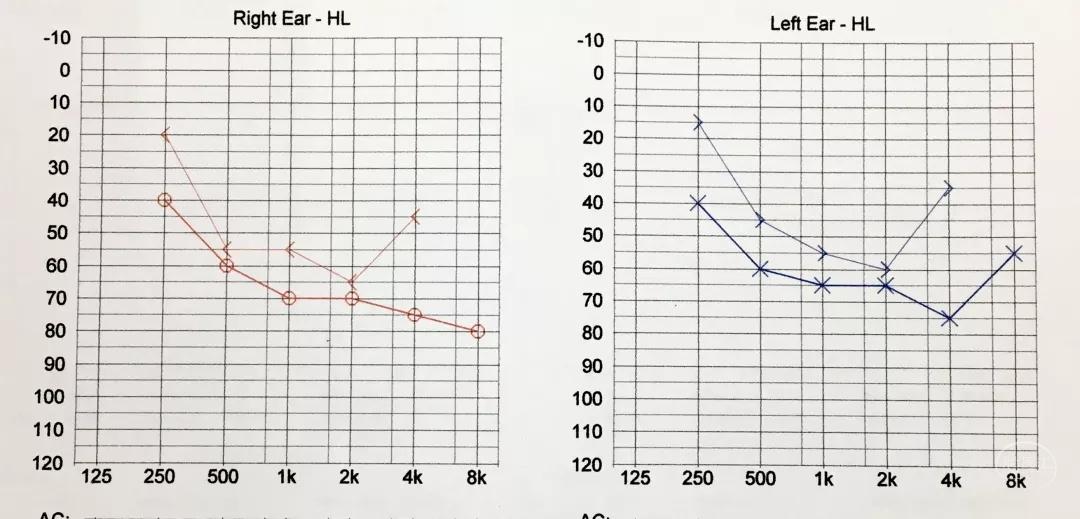

术前听力

术前听力(电测听)